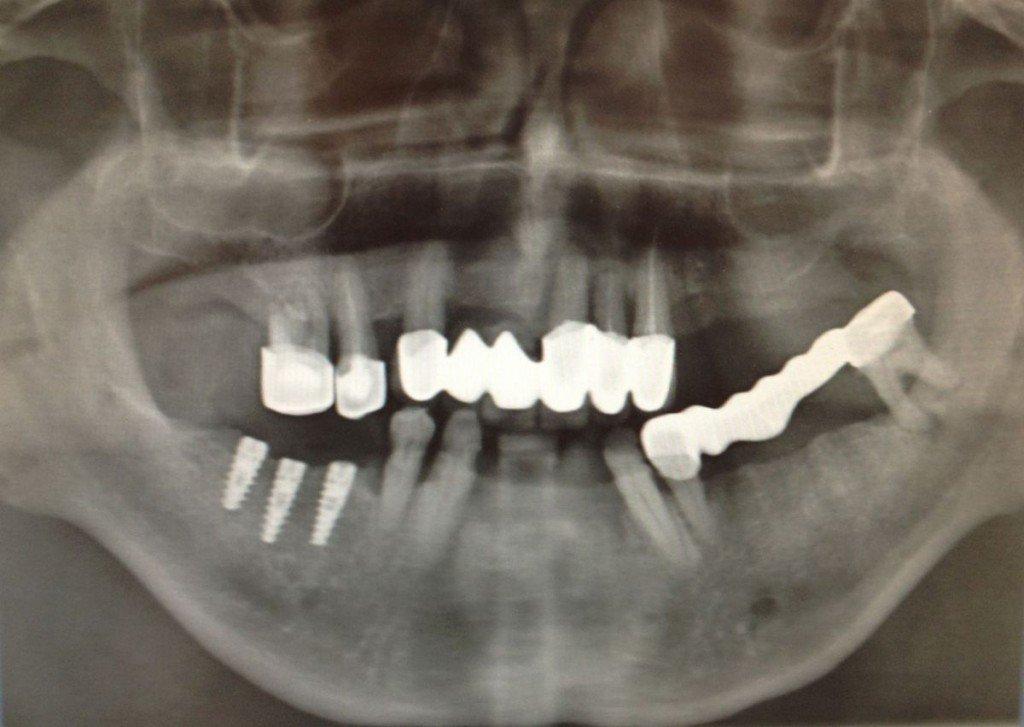

Исследование на рентгене после имплантации зубов

Раздел: Снимки-откровения